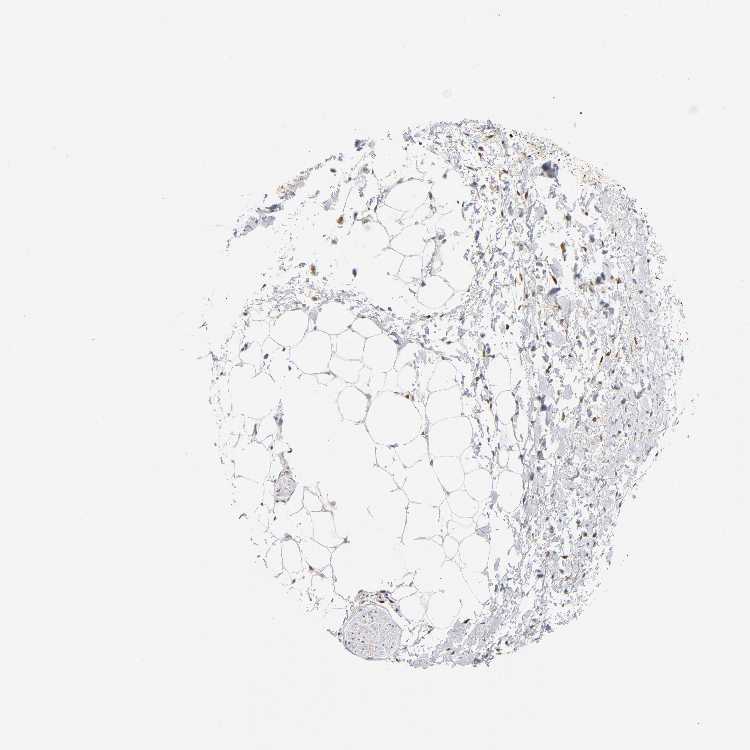

SOFT TISSUE 1 - Antibody stainingi

Antibody staining in the annotated cell types in the current human tissue is reported as not detected, low, medium, or high, based on conventional immunohistochemistry profiling in selected tissues. This score is based on the combination of the staining intensity and fraction of stained cells.

Each image is clickable and will lead to virtual microscopy that enables deeper exploration of all samples and also displays staining intensity scores, fraction scores and subcellular localization as well as patient and tissue information for each sample.

Antibody CAB004328

Chondrocytes Not detected

Fibroblasts Not detected

Peripheral nerve Low